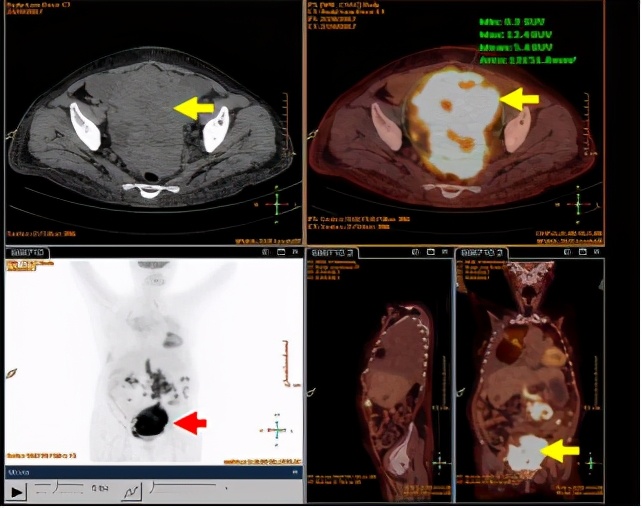

我们决定进一步完善肿瘤相关抗原及全身PET-CT检查行全身筛查,结果提示:癌抗原125:564.22 ↑Ku/L(参考值<35 Ku/L),癌抗原15-3:77.19 Ku/L(参考值<35 Ku/L)。全身PET-CT检查:1、盆腔巨大占位性病变,代谢活性增高(SUVmax值12.4),考虑附件来源恶性肿瘤。2、网膜及系膜多发结节,代谢活性增高,考虑转移。3、腹膜后腹主动脉旁淋巴结,代谢活性增高,考虑转移。4、双肺斑片状高密度影伴结节影,以右肺上叶明显,代谢活性轻度增高,考虑炎性病变,建议治疗后随访复查。5、右肺上叶尖段、左肺上叶尖后段后胸膜下及左肺下叶前内基底段胸膜下钙化灶;双侧胸膜增厚伴胸腔积液,以右侧明显。6、肝囊肿;腹腔及盆腔积液。

行阴道后穹窿穿刺,脱落细胞检查提示:找到癌细胞(腺癌可能)。请肿瘤科会诊后考虑肿瘤为卵巢来源可能性大,建议取活检病理行免疫组化进一步明确来源,患者结缔组织病不除外肿瘤副瘤综合症,目前以治疗肿瘤为主。

图3:PET-CT检查盆腔巨大占位,代谢活性增高,SUVmax值12.4

图4:阴道后穹隆穿刺找到癌细胞(腺癌细胞可能)